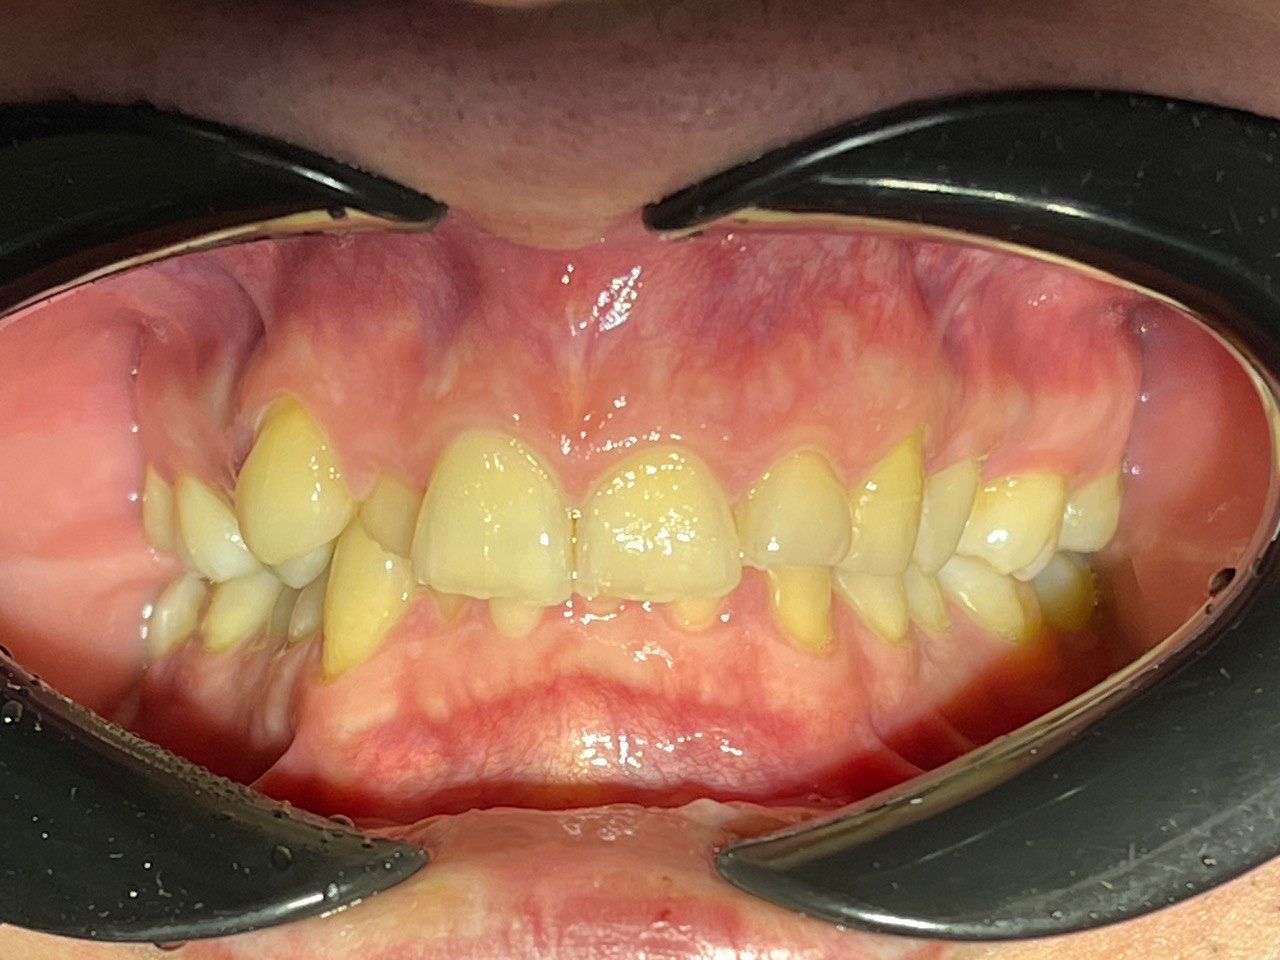

Выявленные проблемы

• Дистальная окклюзия

• Дефицит апикального базиса

• Сужение зубных рядов

• Вестибулярное положение клыков

• Скученность во фронтальных и боковых отделах

Брекет-система Pro